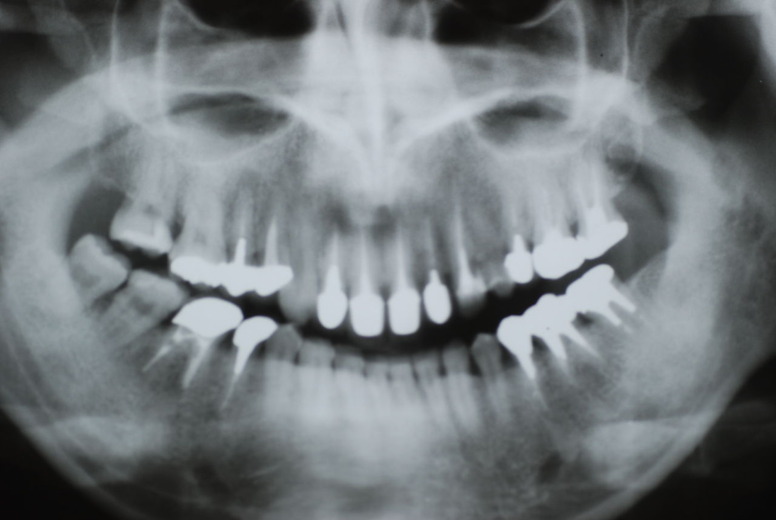

レントゲンでは小さいですが、こう言う虫歯が一番怖いのです。

隣の14歳大臼歯がひどい虫歯になり治療不可能になりつつある状態のレントゲン